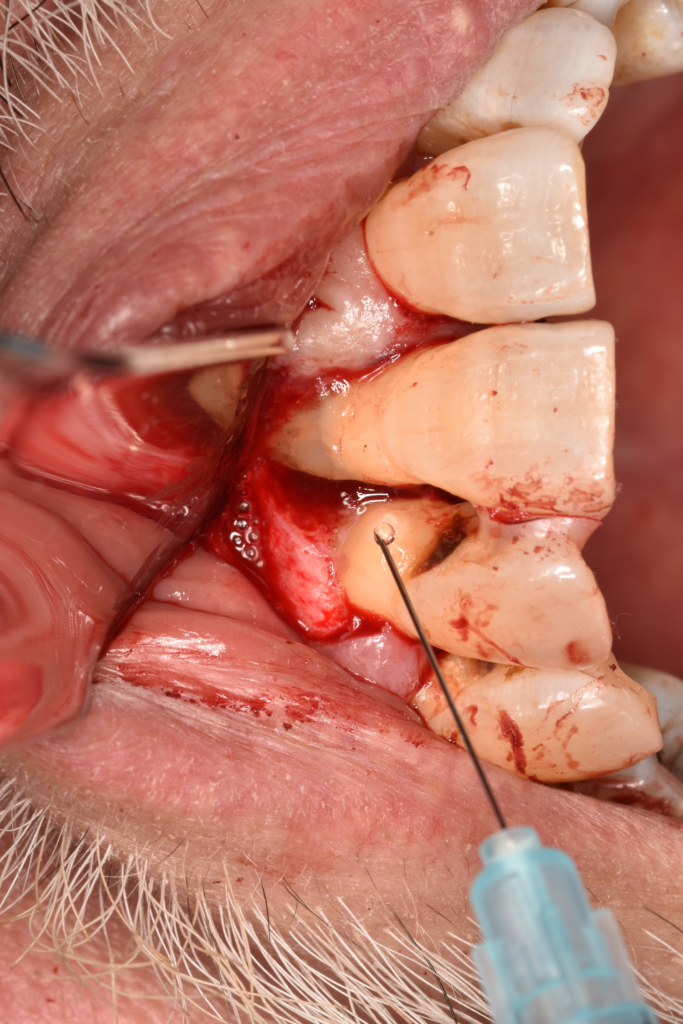

↑歯周外科治療をおこなった後はどうしても歯肉が下がってしまいます。

複数の部位で歯周外科治療をおこないましたが、まだタイミングを探っている場所もあります。SRPの反応を見ながら、介入のタイミングを見ています。